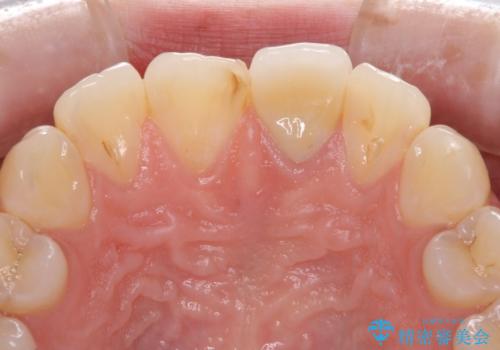

[セラミック治療] 前歯の見た目をきれいにしたい

![[セラミック治療] 前歯の見た目をきれいにしたいの症例 治療前](https://seimitsushinbi.jp/wp/wp-content/uploads/2021/06/968e750651facb819c8d4d824a831cd9-500x350.jpg?v=1622871753)